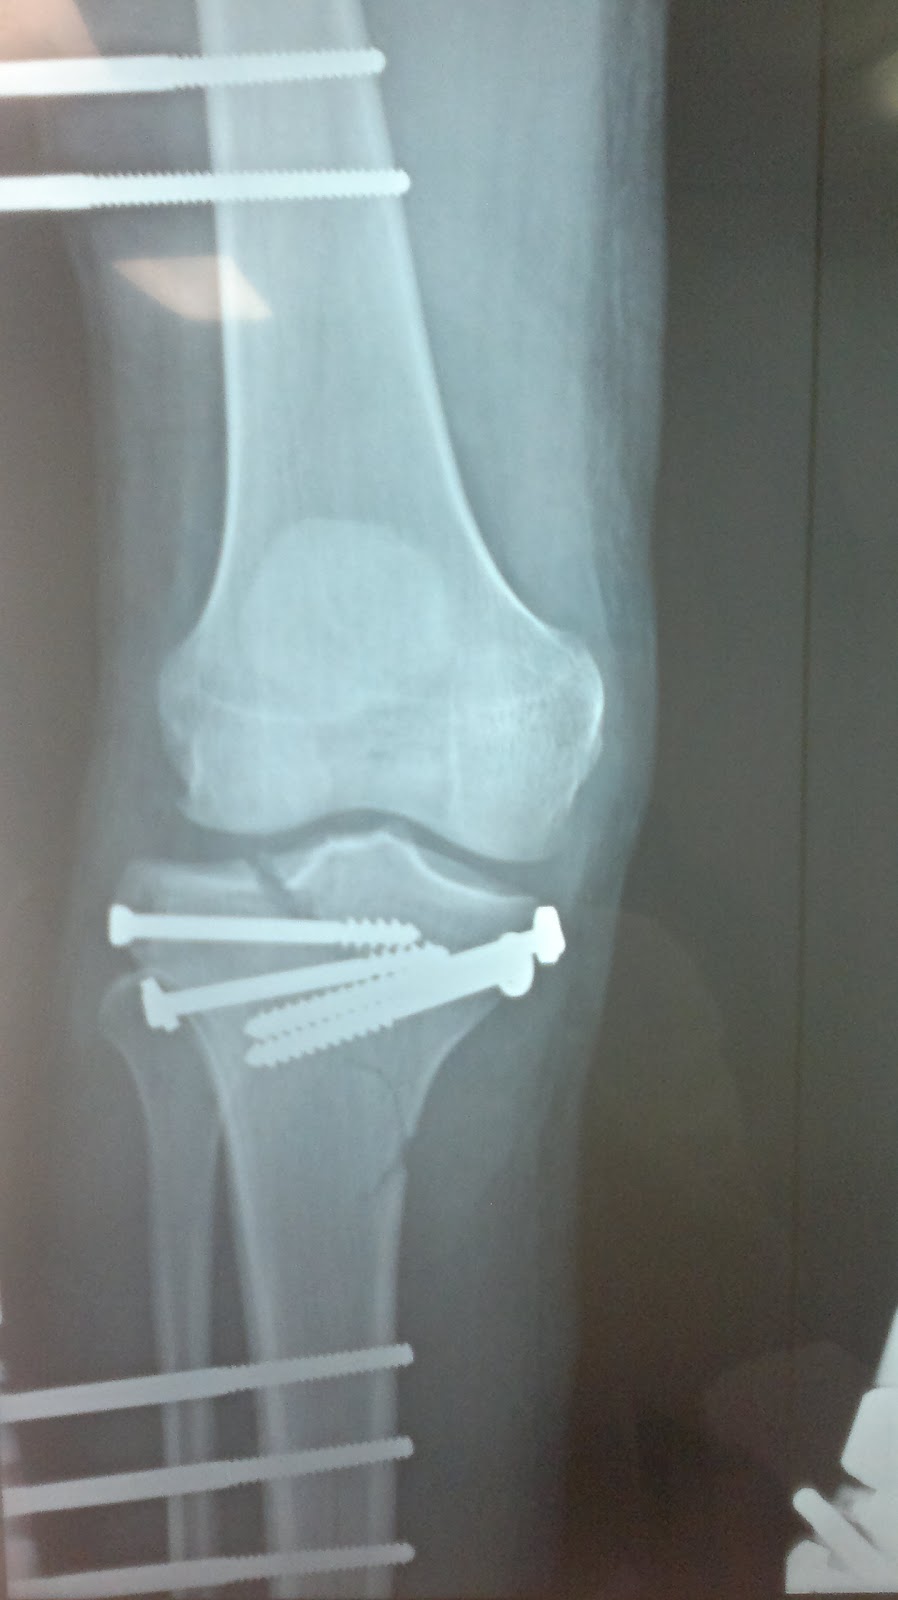

Abordaje posteromedial y colocación de placa en fractura de meseta tibial con fragmento posterior.

Varón 40 años. Fractura bituberositaria de meseta tibial. Radiografía anteroposterior. Osteosíntesis con placa de soporte, tornillos y cerclaje de alambre en la espina tibial.. que en los últimos años se viene usando con más asiduidad en apoyo de las técnicas de osteosíntesis en las fracturas de meseta tibial es la artroscopia 16-18. Clasificación de Moore. Tipo 1: por separación del platillo tibial medial en el plano coronal. Tipo 2: fractura completa del cóndilo, (el trazo de fractura comienza en el compartimento opuesto que se extiende a través de la eminencia tibial). Tipo 3: fractura marginal por avulsión. Tipo 4: fractura marginal, hundimiento del reborde.